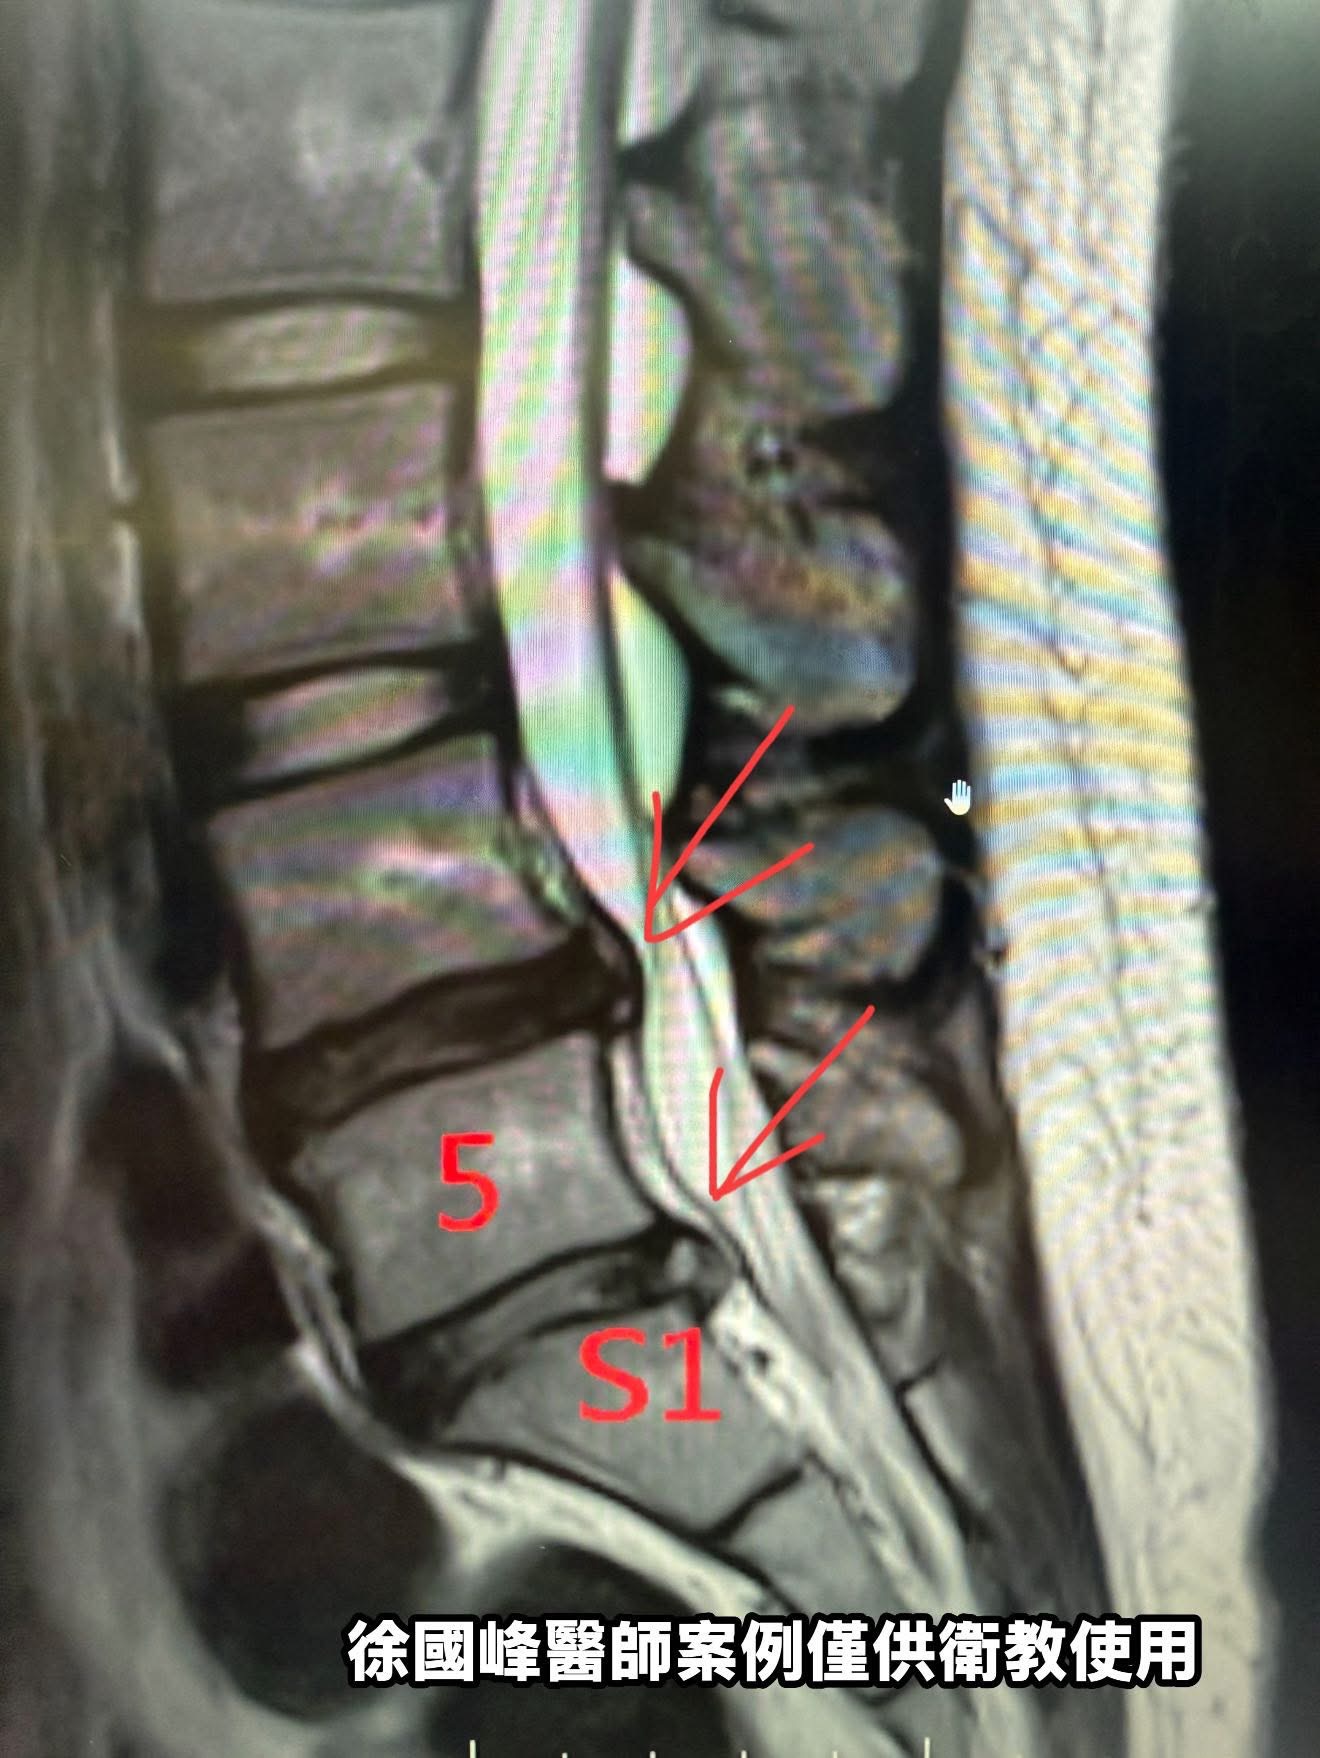

帶著新竹當地大醫院MRI來找我時,那檔案已經拍好一個月。我翻開影像,一目了然:L4/L5與L5/S1兩節椎間盤明顯退化、扁塌、突出,右側神經孔受壓,脊髓硬膜囊也遭擠壓變形。這種變化,若出現在五十歲工地師傅的影像上,我會點點頭說一句「老毛病」;但她才二十歲,年紀之輕,卻有老人的脊椎,MRI所見,椎間盤已出現與年齡不相符的水分流失與突出跡象,形似早期退變」

在許多「年輕型椎間盤突出」案例中,MRI顯示的壓迫雖然來自巨大椎間盤,但導致疼痛最重要的是周邊筋膜緊縮與神經滑動障礙(Neurodynamics restriction)。這類病灶,常常在手術後也無法改善,因為手術切除了突出物,但可能無法有效放鬆卡住神經的筋膜環境。

重建神經滑行空間(針對L5、S1走向)